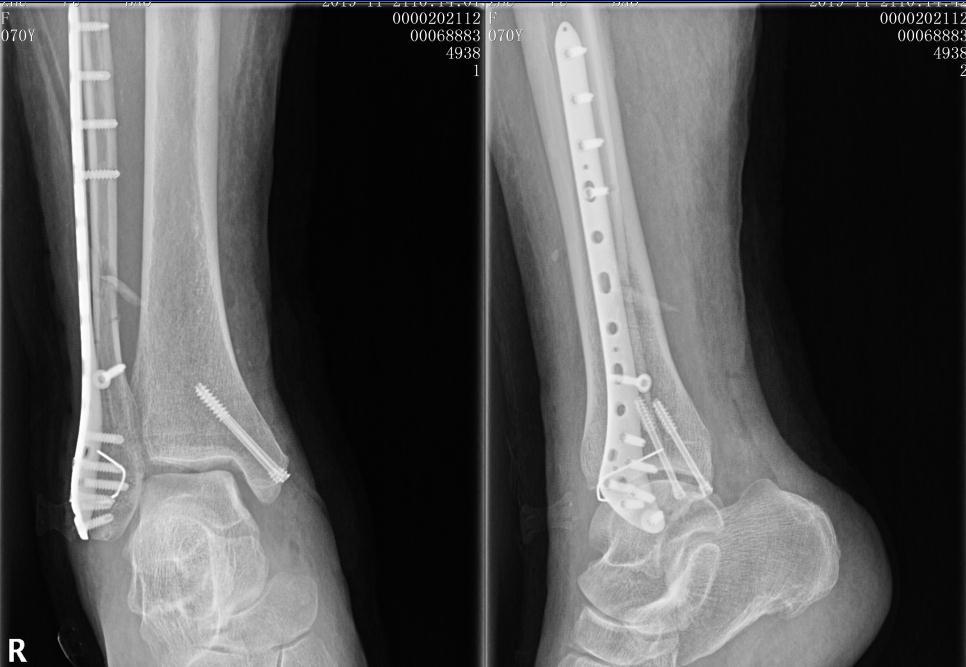

手術一年後,約有33%病患可重回受傷前的基 本日常生活自理,此與年齡、健康狀態及骨折嚴重 程度有相對關係。約有92%的病患未來可以獨立行 走,但僅有41%的病患重回受傷前的行走能力。 另有研究顯示,物理治療頻率,與居家運動執行第3骨片を伴う斜骨折および腓骨近位端骨折を認め た.受傷後12日目に観血的整復を行い髄内釘手術を 行った.術後3週より部分荷重歩行,5週より全荷重 歩行を行い,術後15週の単純x線像にて骨癒合と判脛骨骨幹部、腓骨骨幹部骨折の後遺障害による損害額 後遺障害が認定される場合、逸失利益や後遺障害慰謝料が加算されるので、後遺障害が認定されない場合に比べて損害額は大幅に高くなります。 具体的算定例(40歳男性会社員 年収500万円と仮定した

鋭意リハビリ中腓骨骨折手術から3週間~ 3/23 手術から3週間経過後の検診。 レントゲン、触診にて問題無しとの事。 支えありで片足立ち可能になったのを確認され、松葉杖の取り外し許可が出る。 可動域は逆の足と比べて7割程、この時期でこれ 2/1128までの医療費のトータルは9万7360点 1点=1円です。 これに負担割合をかけますのでおおよそ30万仕事 高いのか安いのかは別にして 私の場合全身麻酔で脛骨に長い (約15cm) プレートを入れました。 手術で2万6000点 麻酔で7800点で 小計3万4000点の 約10万5000 腓骨はとても細い骨ですが、足関節も構成するためとても重要な骨です。 腓骨骨折の手術やリハビリとは? みなさんの周りにも足首を骨折した方がいらっしゃると思います。 足関節の骨折は脛骨や腓骨のくるぶし部分の骨折です。

術のK046 骨折観血的手術の留意事項通知に「前腕骨又は下腿骨骨折の手 術に際し、両骨(橈骨と尺骨又は脛骨と腓骨)を同時に行った場合であっ て、皮膚切開が個別の場合には、別の手術野として骨折観血的手術の「2」 足首の骨折をすると "どのくらいで歩けるようになるのか" 気になりますよね。 私も多くの方から、このようなご質問をよく聞かれます。 今回はそんな疑問にお応えし、 足首の骨折後はどのくらいで歩けるようになるのか 、 ちゃんと歩けるようになるのか ご紹介 します。